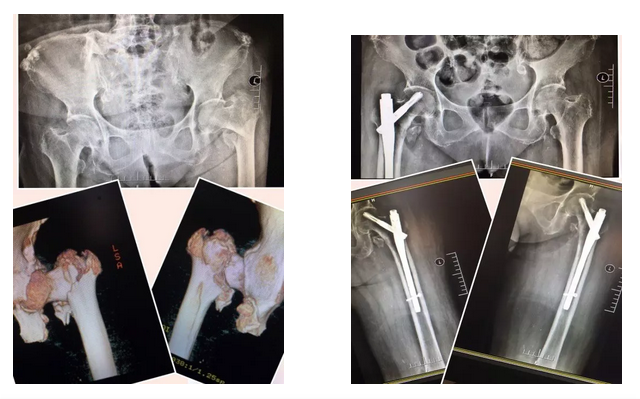

77岁的华大妈,因右侧股骨近端粉碎性骨折于9月26日来到青岛西海岸新区中医医院骨伤二科住院治疗,入院后,郑鹏副主任为其进行仔细诊查,并根据患者病情,设计了一套诊疗方案,在完善相关检查、排除了手术禁忌、与患者家属沟通后,9月29日为华大妈成功的实施了闭合复位PFNA内固定术。